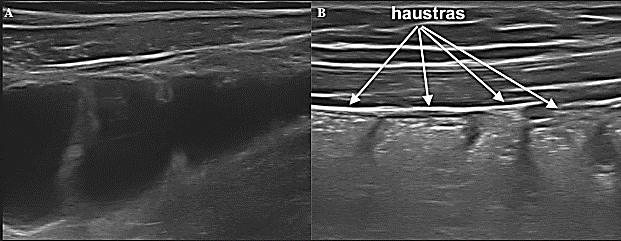

Enfermedad de Crohn: De acuerdo investigaciones de diversos autores, se ha mostrado la alta sensibilidad y precisión que tiene la ecografía digestiva en pacientes pediátricos para detectar sospechas de EC, en estos se describe la exactitud de la técnica en la detección del engrosamiento de la pared en comparación con otras técnicas de imagen como la TC y RM, con una especificidad de más del 90 %, concluyendo que es un medio apropiado para confirmar o descartar su presencia. [20], [23] Varios estudios también expresan mejores resultados en la detección de la enfermedad en el íleon, colon ascendente o descendente, los cuales se han observado marcadamente afectados de forma discontinua, con rigidez o disminución de la peristalsis, también es frecuente observar engrosamiento de la submucosa sobre todo si la enfermedad tiene cierto tiempo de evolución, mientras que la sensibilidad es más baja es para las lesiones situadas en yeyuno o en el recto. [20], [22] Además, con sondas de alta frecuencia es posible observar trayectos hiperecogénicos o hipoecoicos lineales (según contengan gas o no) que atraviesan las capas en profundidad y las cuales corresponden a ulceraciones que van a condicionar mayor o menor desestructuración del patrón de capas. ( IMAGEN 3 ).

Figura 3: Corte transversal de un asa intestinal donde se muestra los datos ecográficos característicos de la afectación por EC. (15)